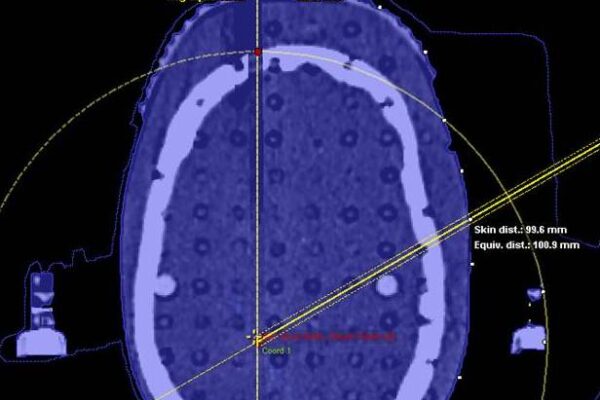

- The Use of Hybrid Imaging in Radiotherapy Treatment Planning